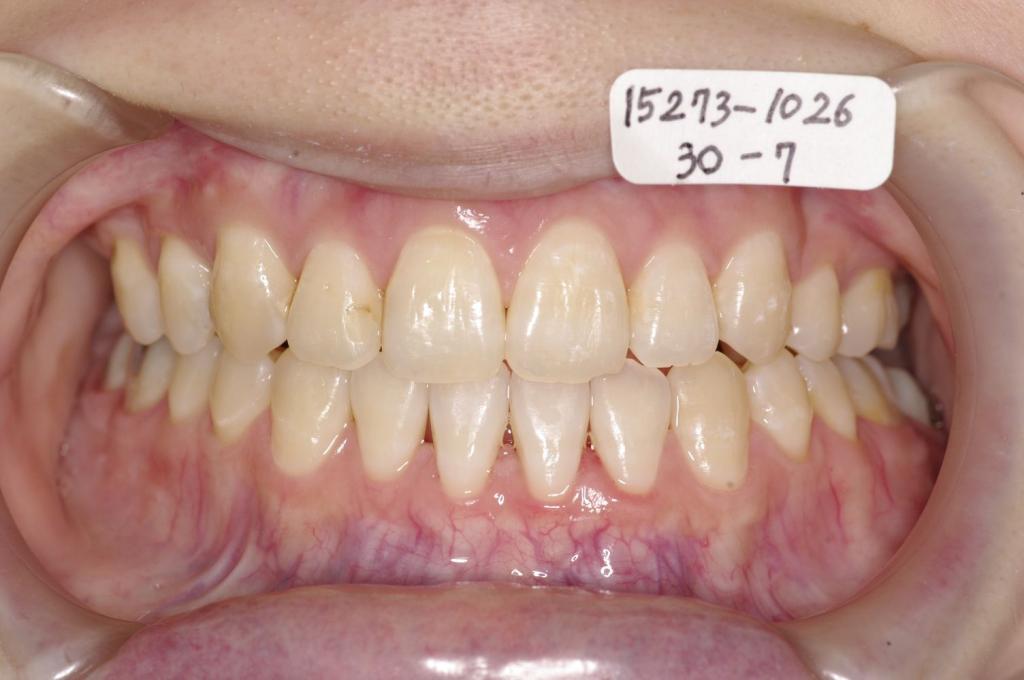

下記の実績データをクリックして頂くと「性別」、「治療開始年齢」、「治療終了年齢」、「治療方法(矯正治療装置写真含む)」、「治療終了までの費用」など、詳細な矯正治療データをご覧頂けます。